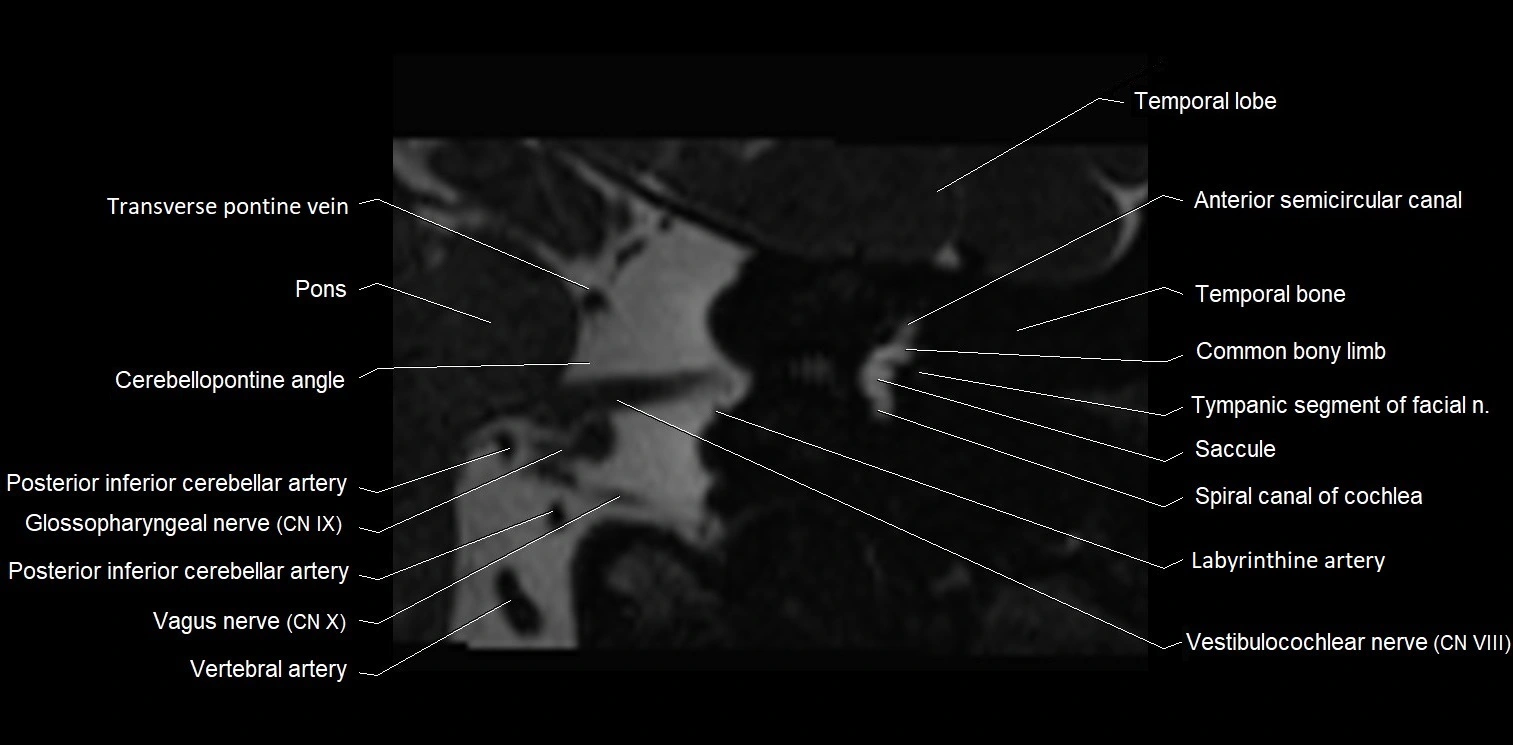

MRI images

image